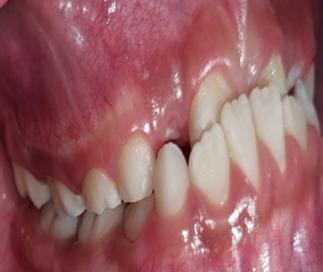

Sinodoncia vs esquizodoncia, reto diagnóstico para el odontólogo synodontics vs skizodontics, a diagnostic challenge for the dentistry

María Liliana Ríos Antezana, Carmen Adriana Blanco Lafuente